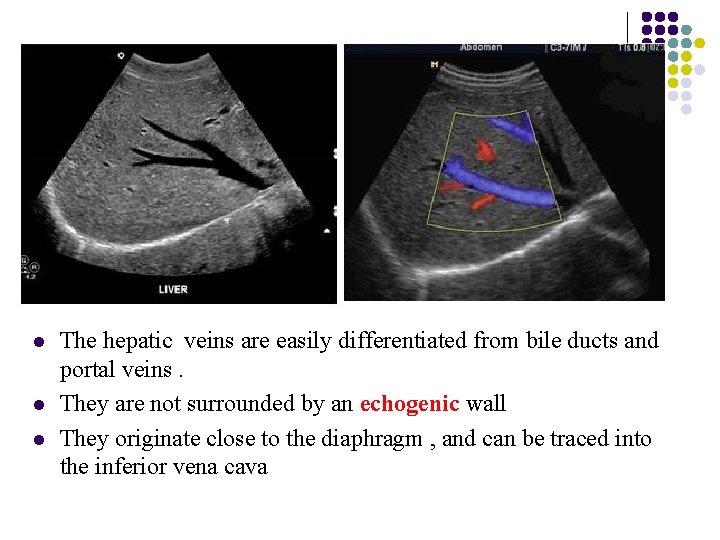

Distinguishing Characteristics of Hepatic and Portal Veins l The best way to distinguish the hepatic from the portal vessels is to trace their points of entry to the liver. The hepatic vessels flow into the inferior vena cava, whereas the splenic veins and superior mesenteric vein join together to form the portal venous system.

Distinguishing Characteristics of Hepatic and Portal Veins l The walls of hepatic veins are thin-walled , and the walls of portal veins are brightly reflective veins

l l l The hepatic veins are easily differentiated from bile ducts and portal veins. They are not surrounded by an echogenic wall They originate close to the diaphragm , and can be traced into the inferior vena cava